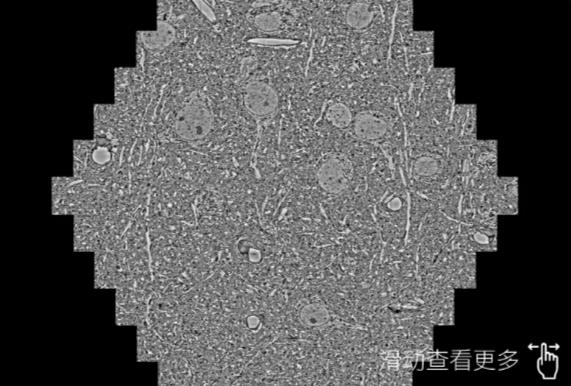

鼠脑切片。左图使用崇明蔡司崇明扫描电镜MultiSEM706对165μmx143pm面积区域成像,耗时仅需1.5秒。右图为鼠脑切片中30μm区域放大效果。样品由芝加哥大学B.Kasthuri提供。

使用蔡司高速崇明扫描电镜MultiSEM对1mm²人脑皮层组织进行高分辨成像,并对其中的各种细胞结构进行三维重构分析。左图展示了2x3mm²组织平面中锥体神经元的三维重构效果。右图显示了局部体积神经元三维重构。图像由哈佛大学chtman实验室提供,渲染图由D. Berger 制作。